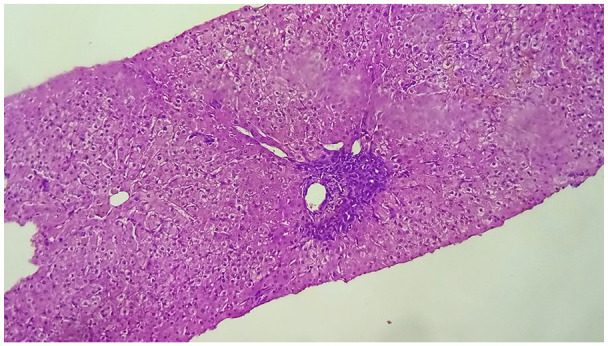

Methimazole is commonly prescribed for patients with hyperthyroidism. It typically exhibits a well-tolerated profile, with common side effects including gastrointestinal disorders and rash. However, more serious rare yet adverse reactions, notably agranulocytosis and hepatotoxicity have been documented in literature. Here we present a case of a 27-year-old female, recently diagnosed with Graves' disease, who was prescribed methimazole and developed severe pruritus with cholestatic jaundice 13 days later. Concomitant causes of liver disease were ruled out. The treatment was discontinued, and a switch to corticosteroid therapy with a regimen of radioactive iodine sessions was initiated. The patient's condition showed a resolution of pruritus and jaundice, a disappearance of cytolysis with an aggravation of cholestasis followed by a gradual decrease, leading to the liver function normalization after 2 years. Methimazole-induced cholestatic jaundice is a rare yet severe adverse effect. Patients should be aware of this complication and advised to immediately stop taking the treatment when suggestive symptoms (pruritus, jaundice, dark urine, light-colored stool) occur.